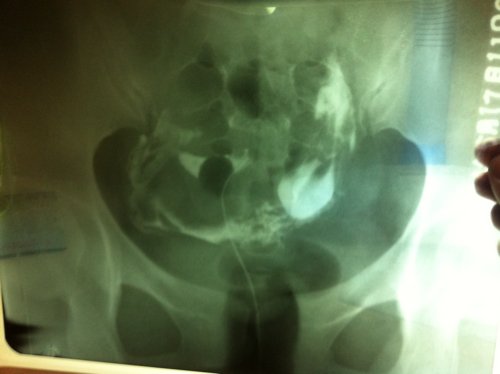

朋友今天做的输卵管造影拍的两张片子,请医生看看是不是真的粘连了,需要做腹腔镜手术吗?另外,做这种检 朋友今天做的输卵管造影拍的两张片子,请医生看看是不是真的粘连了,需要做腹腔镜手术吗?另外,做这种检查应该都有一份报告单吧?可我朋友说医生没给,只是一味的叫她做手术。请医生指导一下。 点击展开 匿名用户 2014-05-17 23:48 为您推荐: 其他回答 病情分析: 进行宫腔镜联合术来治疗比较好。 指导意见: 去当地3甲医院治疗.设备和治疗技术是最好的,积极配合医生治疗,祝早日康复 衡夏兰_smlN 2014-05-18 10:07 相关问题 输卵管部分粘连,不是很严重,医生让我做腹腔镜手术,我想问有必要做吗?不做的话,有别的方法可以治疗吗 请问,我11月24日做X光造影,12月31日做腹腔镜手术,1月26日医生要求我同房 如果成功受孕 如果6月份陪朋友做ct片子,当时医生让我在里边照看着,当时也不知道自己怀孕了,7月份就检查出怀孕了